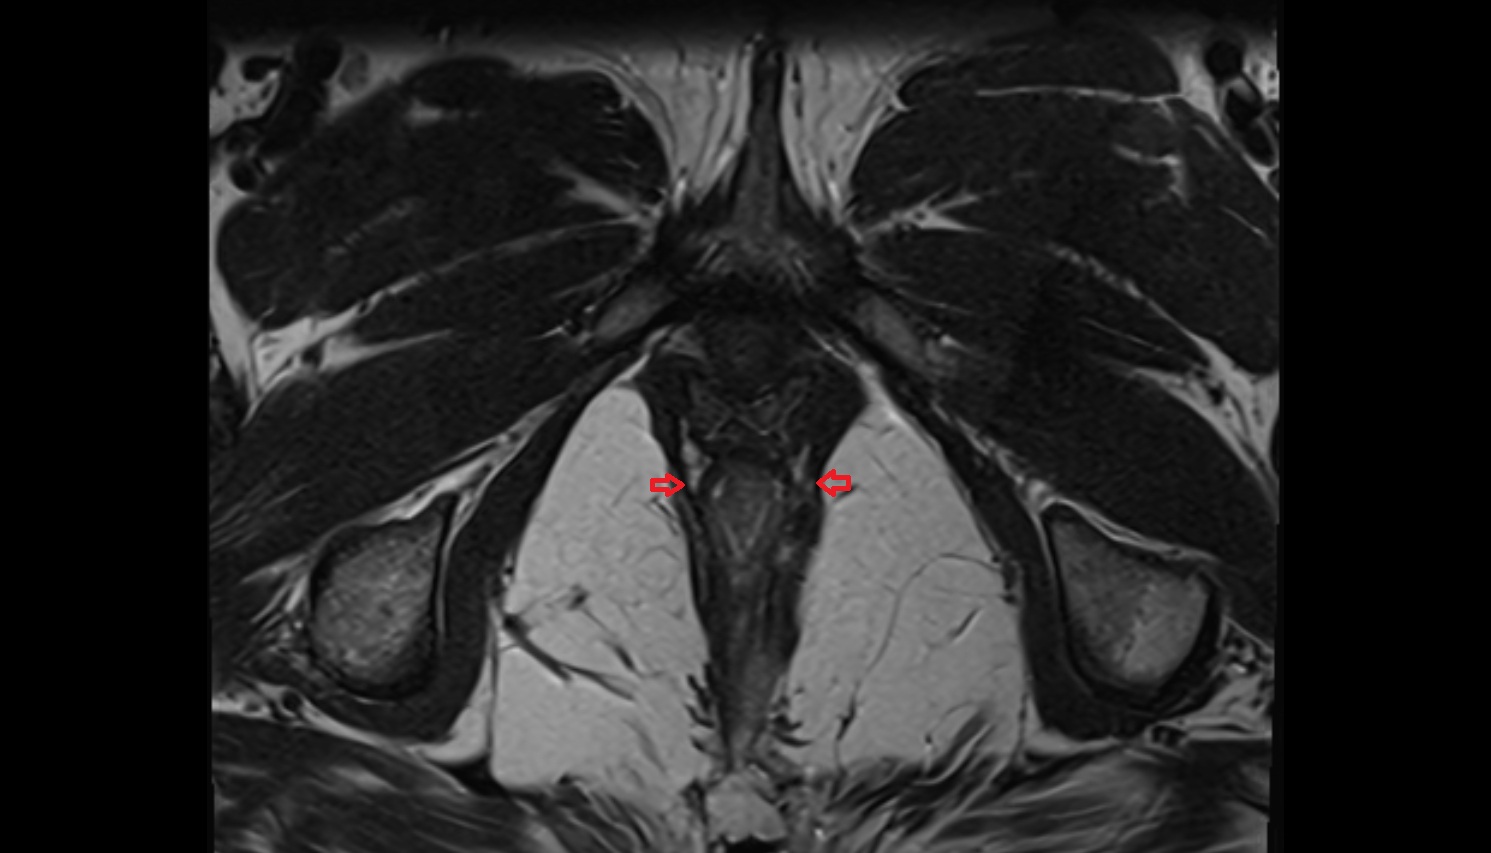

- Corpus cavernosum

- Corpus spongiosum

- Bulb of Penis

- Crus of penis